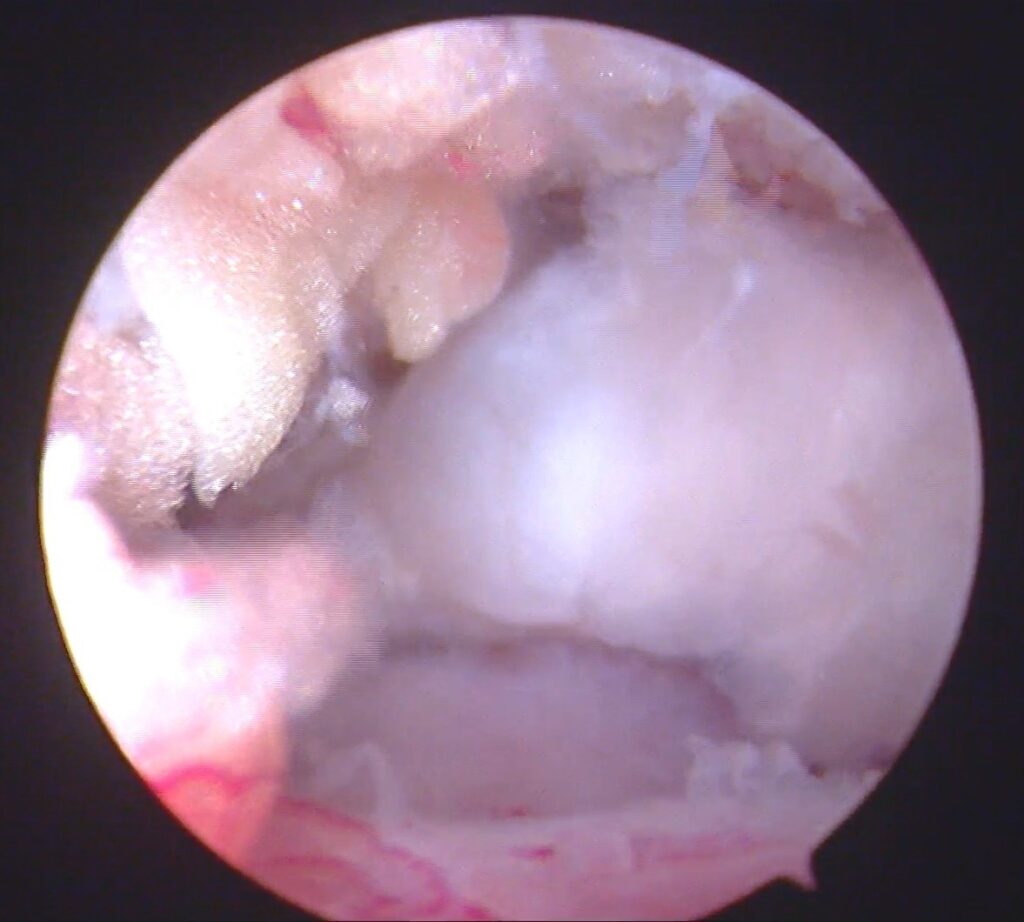

„Jei plyšusios sausgyslės susiūti neįmanoma, panaudojama donorinė sausgyslė, iš kurios suformuojamas lopas pritvirtinamas taip, kad prilaikytų žastikaulio galvą ir judesio metu neleistų jai kilti, t.y. pakeičiama sąnario judesio biomechanika. Tokia operacija yra artroskopinė, atliekama per mažus pjūvelius, panaudojant vaizdo kamerą. Pacientas išvaduojamas nuo skausmo ir atkuriami rankos judesiai“.

Peties sausgyslių atroskopinė operacija